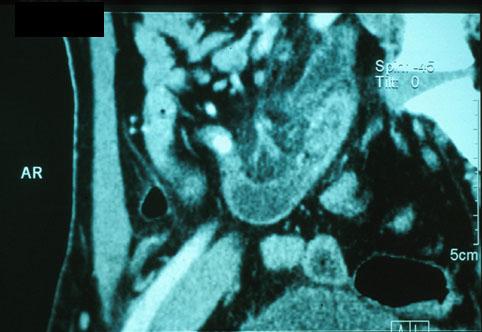

Apendicitis Flegmonosa acompañado de litiasis (Caso presentado por el Centro de Tratamiento Médico Hospital Nacional de Nagasaki)

Enfermedad Inflamatoria - Ulcerativa/otros

colon/apéndice cecal

Resonancia Magnética